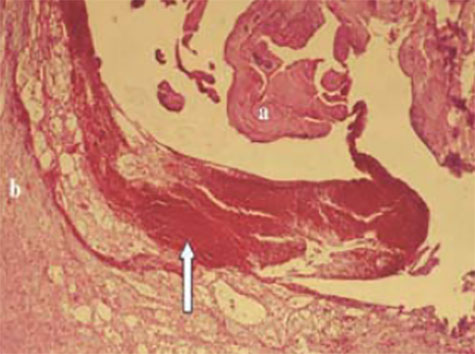

7.- Lesión inicial. Haemorragias (flecha) entre el tendón (a) y la vaina del tendón (b), Н/Е, barra de escala = 3m.